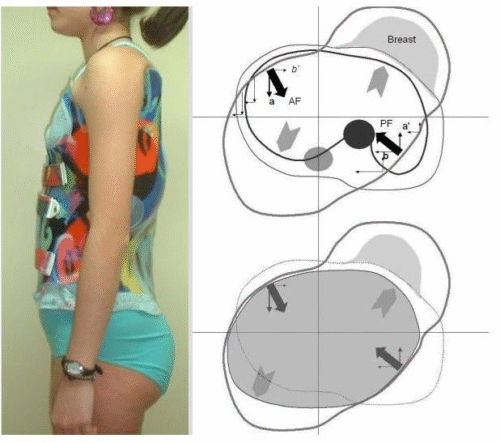

المسح ثلاثي الأبعاد لجسم المريض: حيث يتم عمل مسح كامل للجذع لتحديد مناطق الانحراف بدقة عالية، وهذا يسمح بتخطيط أكثر دقة من الطرق التقليدية.

إنشاء نموذج افتراضي متناظر: يُستخدم هذا النموذج لعكس صورة الجذع بحيث تمثل النسخة المثالية للجسم، مما يسهل مقارنة الشكل المثالي بالجسم الفعلي.

مقارنة الصورة الأصلية بالنموذج الافتراضي: تُستخدم الخرائط اللونية لتوضيح المناطق التي يتجاوز فيها الانحراف 6 ملم، وبالتالي تحديد نقاط الضغط داخل الحزام بدقة.

تخصيص الحزام حسب حاجة كل مريض: يتم تصميم وسائد الضغط بناءً على التحليل الثلاثي الأبعاد، لضمان توجيه القوى التصحيحية نحو مناطق الانحناء الحقيقية، بدلاً من الاعتماد على التقدير البصري فقط.

وبالتالي، يتم الجمع بين الدقة العلمية وراحة المراهق أثناء ارتداء الحزام، مما يحسن النتائج النهائية للعلاج.